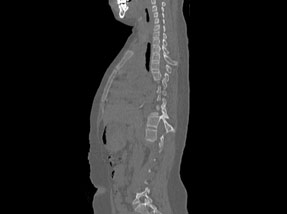

• Pre-SurgeryBefore

Case 1